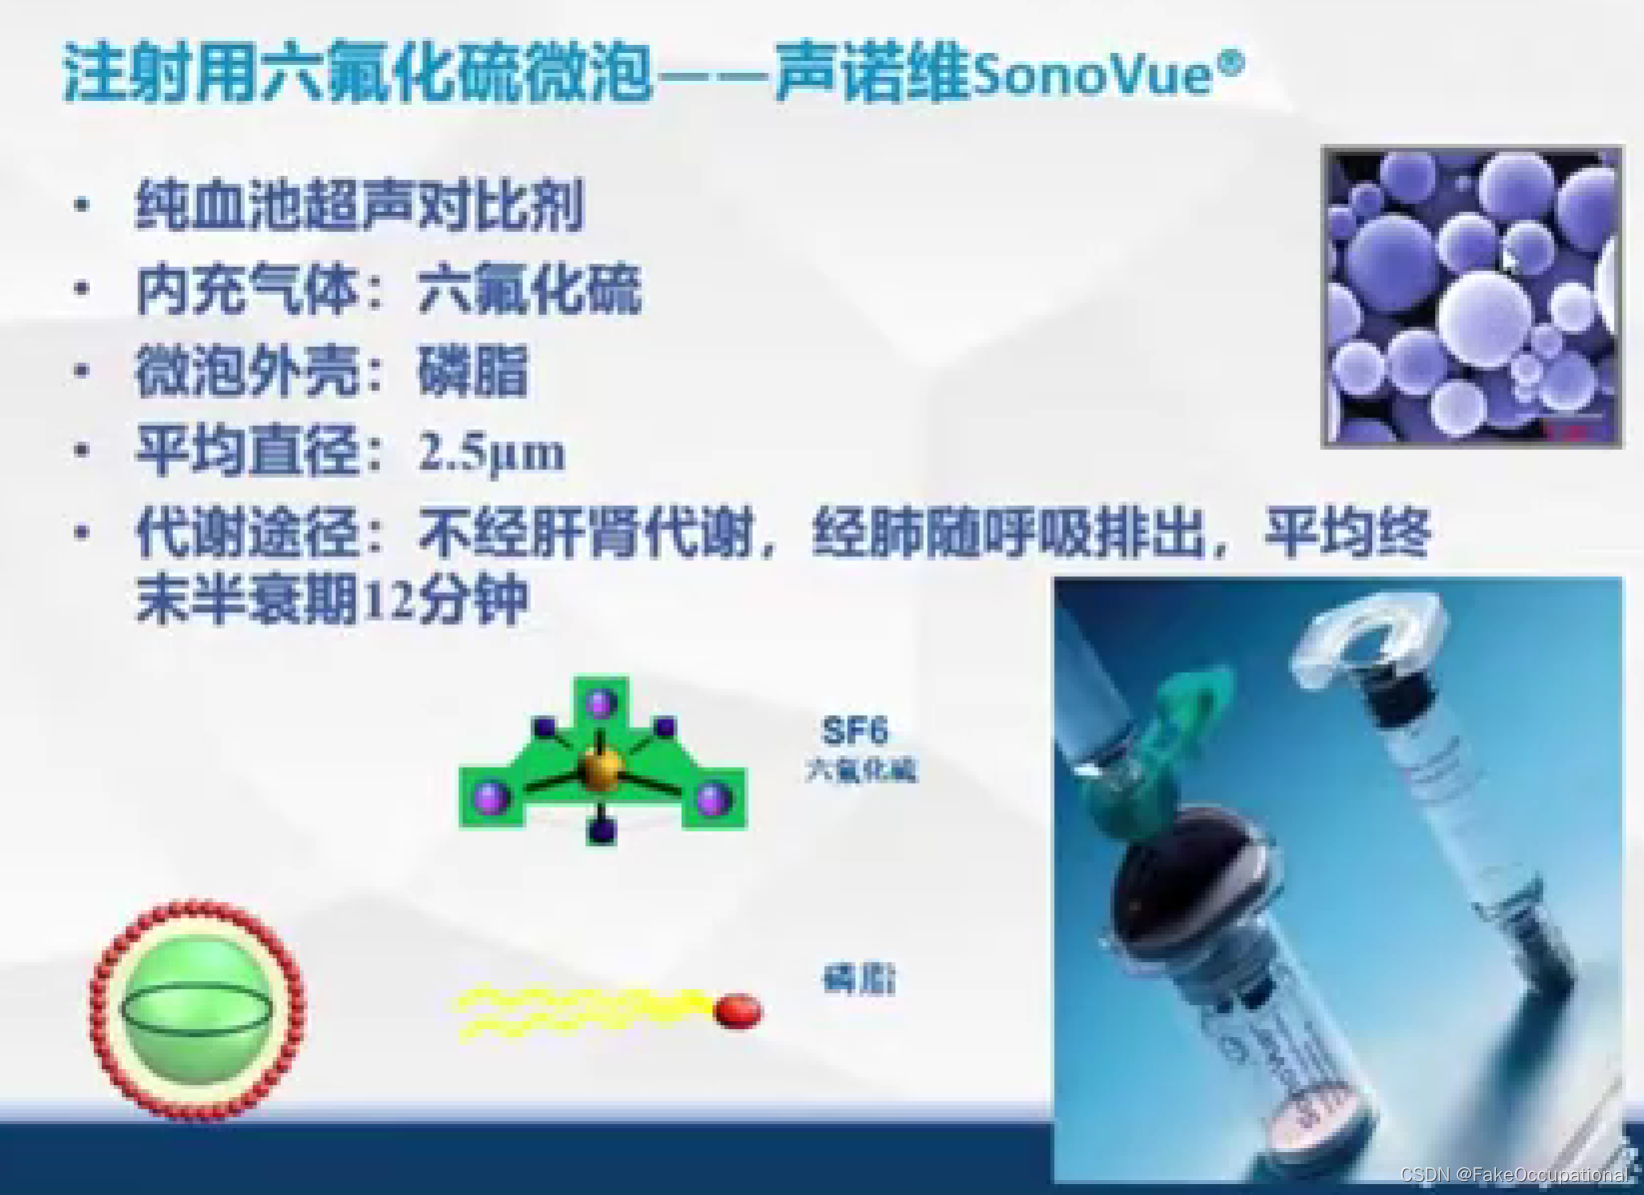

超声新技术

2.超声造影

- 超声造影